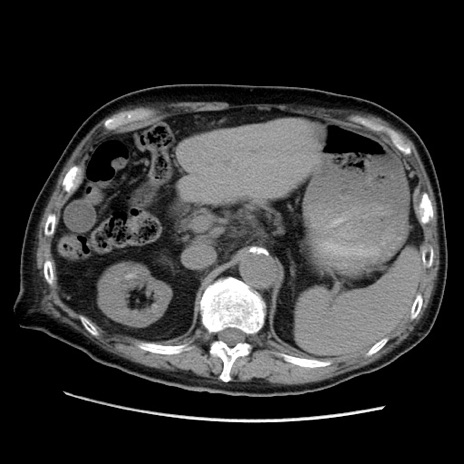

症例21(横断像)

【症例】70歳代男性

【主訴】腹痛

【現病歴】肝硬変・肝細胞癌にてかかりつけの方。約9時間前に食後より腹痛出現。症状が徐々に増悪し、嘔吐出現したため来院。

【既往歴】肝硬変、肝細胞癌(RFA、TACE後)

【身体所見】意識清明、表情苦悶様、BT 36℃、BP 129/78mmHg、P 88bpm、SpO2 97%(RA)、右上腹部から心窩部にかけて圧痛あり、反跳痛なし、筋性防御あり。

【データ】WBC 5800、CRP 0.16